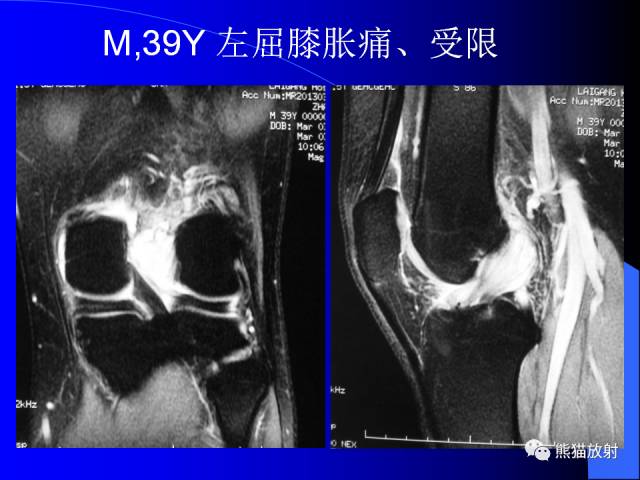

膝关节周围囊肿MRI

膝关节周围囊肿是较常见的病变,可以是原发的,多见于青年及儿童,囊内容物通常是黏液;也可以是继发的,多与关节腔相通,内含一般黏性的滑液,常继发于膝关节骨关节炎、类风湿关节炎、非特异性滑膜炎、半月板损伤、髌骨软骨软化症等。

腘窝囊肿是膝关节周围最常见的囊肿。